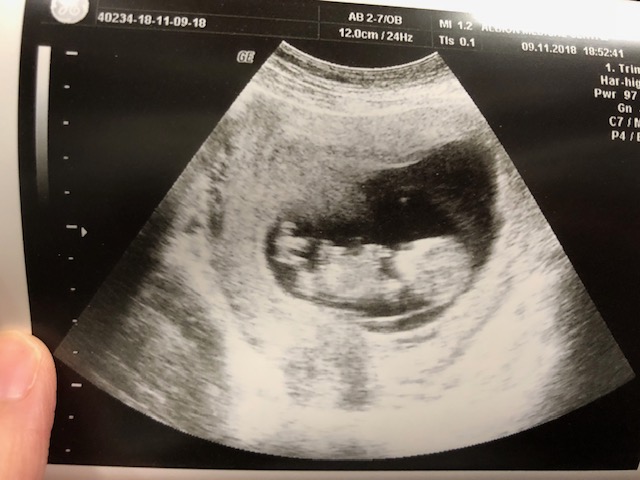

這輩子,大概只有這40個星期,有人與你「合二為一」。她/他從你懷孕的第一天開始便與你的生活同步:一同上班,一同食飯,一同睡覺;無論你開心或生氣,她/他也感覺到。這種親密的感覺,對懷胎十月的媽媽來說,實在刻骨銘心。

的確,懷孕時承受的辛酸不少:孕吐、失眠、胃酸倒流、水腫、恥骨痛等等,都叫孕媽媽度日如年。不過,當你感到第一次胎動時,那種感動,可會教人忘記辛苦的感覺。還記得陀著唯妹感到第一次胎動時,是她半夜在打嗝,那種感覺很奇妙。

還有不夠一個月,唯妹就要出世了,我知道「卸貨」後,我將會很懷念這種痛苦但甜蜜的感覺。正在懷孕的你,要好好珍惜啊!